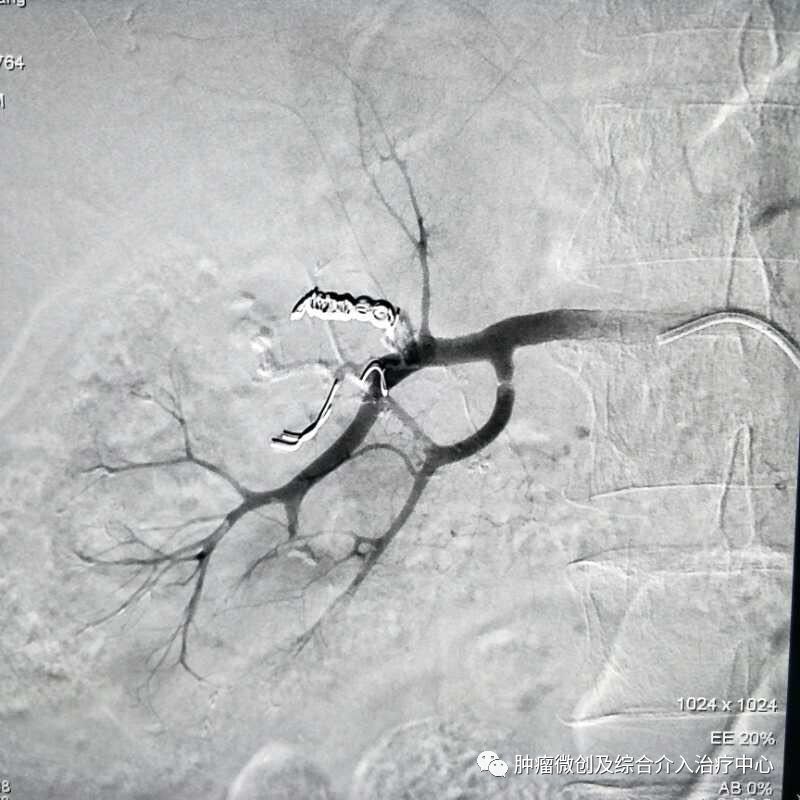

( DSA造影提示胃十二指肠分支血管出血)

运城第一医院肿瘤介入科专家,运城市第一医院介入科专家